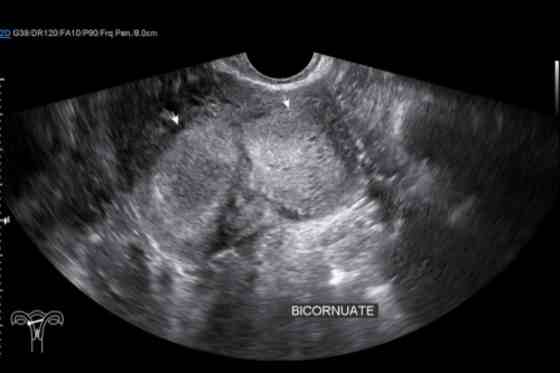

ecografie transvaginala: prima metoda de diagnostic care poate evidentia forma anormala a uterului;

rezonanta magnetica nucleara (RMN): ofera imagini detaliate ale uterului si poate confirma prezenta unui uter bicorn;